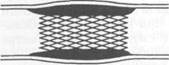

Хирургические методы лечения. Классические реконструктивные оперативные вмешательства можно разделить на четыре группы: I) эндартерэктомия — операция с удалением пораженной интимы; 2) шунтирование; 3) протезирование; 4) эндолюминальная дилатация, дилатация с установкой стента. Больным с сегментарными окклюзиями артерий, не превышающими по протяженности 7—9 см, показана эндартерэктомия. Операция заключается в артериотомии и удалении измененной интимы вместе с атероскле-ротическими бляшками и тромбом. Операцию можно выполнить как закрытым (из поперечного разреза артерии), так и открытым способом (рис. 18.2; 18.3). При закрытом способе имеется опасность повреждения инструментом наружных слоев артериальной стенки. Кроме того, после удаления интимы в просвете сосуда могут остаться ее обрывки, благоприятствующие развитию тромбоза. Вот почему предпочтение следует отдавать открытой эндартерэктомии, при которой производят продольную артериотомию над облитерированным участком артерии и под контролем зрения удаляют измененную интиму с тромбом. Для предупреждения сужения просвет рассеченной артерии может быть расширен путем вшивания заплаты из стенки подкожной вены. При операциях на артериях крупного калибра испольуют заплаты из синтетических тканей (политетрафторэтилен). Некоторые хирурги применяют ультразвуковую эндартерэктомию.

Рис. 18.3. Открытая эндартерэктомия.